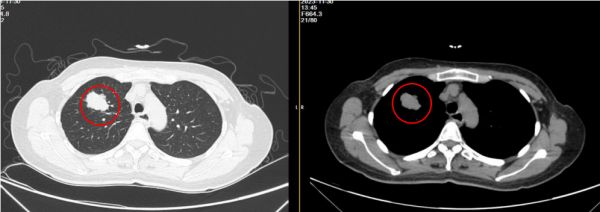

我院神经内二科杜浩勇医生接诊了患者。经详细追问病史,了解到患者既往体健。查体未见明显阳性体征。MR颅脑平扫+增强显示患者颅内软脑膜及所示颈髓软脊膜广泛异常强化,不排除颅内感染、脑膜转移可能(见图一),遂给予患者行肿瘤标志物检查。结果提示癌胚抗原34.70ng/ml,高;糖类抗原199:32.50U/mL,高;糖类抗原125:44.20U/mL,高;糖类抗原153:27.80U/mL,高。患者肺部CT提示右肺上叶尖段占位,考虑周围型肺癌;食管中下段稍扩张,胃底壁可疑增厚(见图二)。腰椎穿刺显示:白细胞计数35×106/L,高;脑脊液蛋白(CSFP)1.24g/L,高;细胞学呈淋巴-单核细胞反应型,以淋巴细胞为主,可见异形细胞,考虑肿瘤细胞可能性大。

图一:颅内软脑膜及所示颈髓软脊膜广泛异常强化,不排除颅内感染、脑膜转移可能。